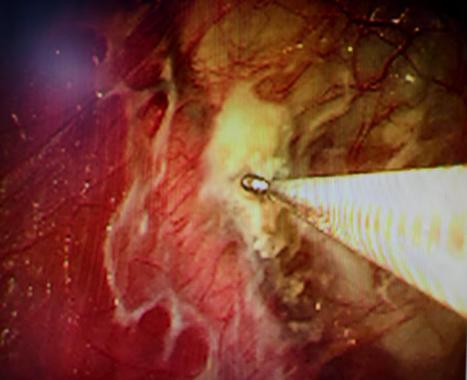

近期,国内知名呼吸介入专家陈愉教授联合我院呼吸与危重症医学科团队,为李先生施行“胸腔镜下肺大疱探查术 + 胸腔闭式引流术”。手术中,陈愉教授运用单孔胸腔镜技术,仅在患者胸壁开了一个1cm的小切口。通过高清胸腔镜系统探查发现,患者胸腔内存在广泛粘连以及多发微小肺大疱,肺叶解剖结构异常,肺门血管直接暴露,经判断肺大疱腔已与胸腔贯通。

(胸腔镜下可见胸腔粘连、多个微小肺大疱)